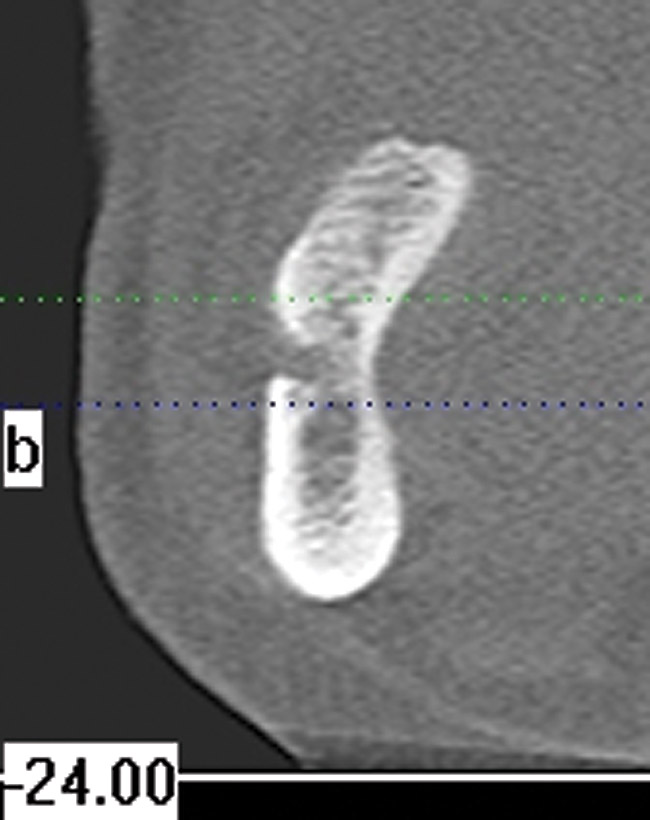

The use of cone-beam computed tomography (CBCT) has revolutionized clinical diagnostic abilities. Featuring advantages such as a relatively small size, less radiation exposure, and lower cost, CBCT has gained popularity by improving predictability and the quality of care in implant dentistry. This technology has value in aiding in the diagnosis of root fractures. Recently, a study found dental CBCT exhibited greater accuracy (62.8% versus 54.5%) in helping to diagnose vertical root fractures than conventional radiography. The investigators concluded that use of dental CBCT is effective for the diagnosis of root fractures regardless of the direction.3

CBCT has been available for craniofacial imaging since 1999 in Europe and since 2001 in the United States. The scanner uses a cone-shaped x-ray beam rather than a conventional linear fan beam to provide images of the skull's bony structures. CBCT uses a square 2-dimensional (2-D) array of detectors to capture the cone-shaped beam. Subsequently, reconstruction software is applied on the CBCT volumetric data to produce a stack of 2-D gray-scale level images of the anatomy.